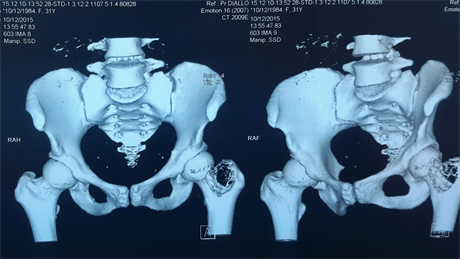

CT showed a tissue osteolysis of 49 × 40 × 39 mm of the neck and the greater trochanter with the upper cortex almost broken without periosteal reaction or medullary perilesional condensation. The surrounding soft tissues were free of abnormalities (Figure 2).

Figure 2. CT showing the osteolysis and soft tissues free of abnormalities.